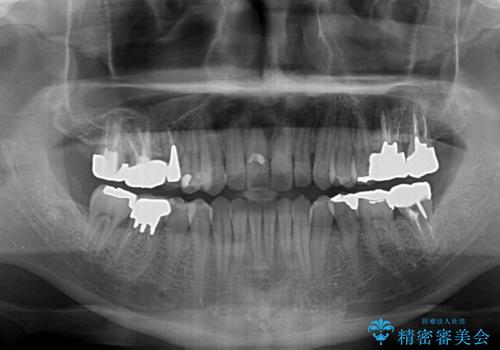

受け口傾向の咬み合わせ 前歯のデコボコをワイヤー矯正で素早く改善

前歯のクロスバイトは、改善の途中で歯髄壊死を起こすリスクが高くなるため、マウスピース矯正よりもワイヤー矯正をお勧めしております。

この患者様もクロスバイトはあっという間に改善され、1年強で速やかに治療を終えることができました。